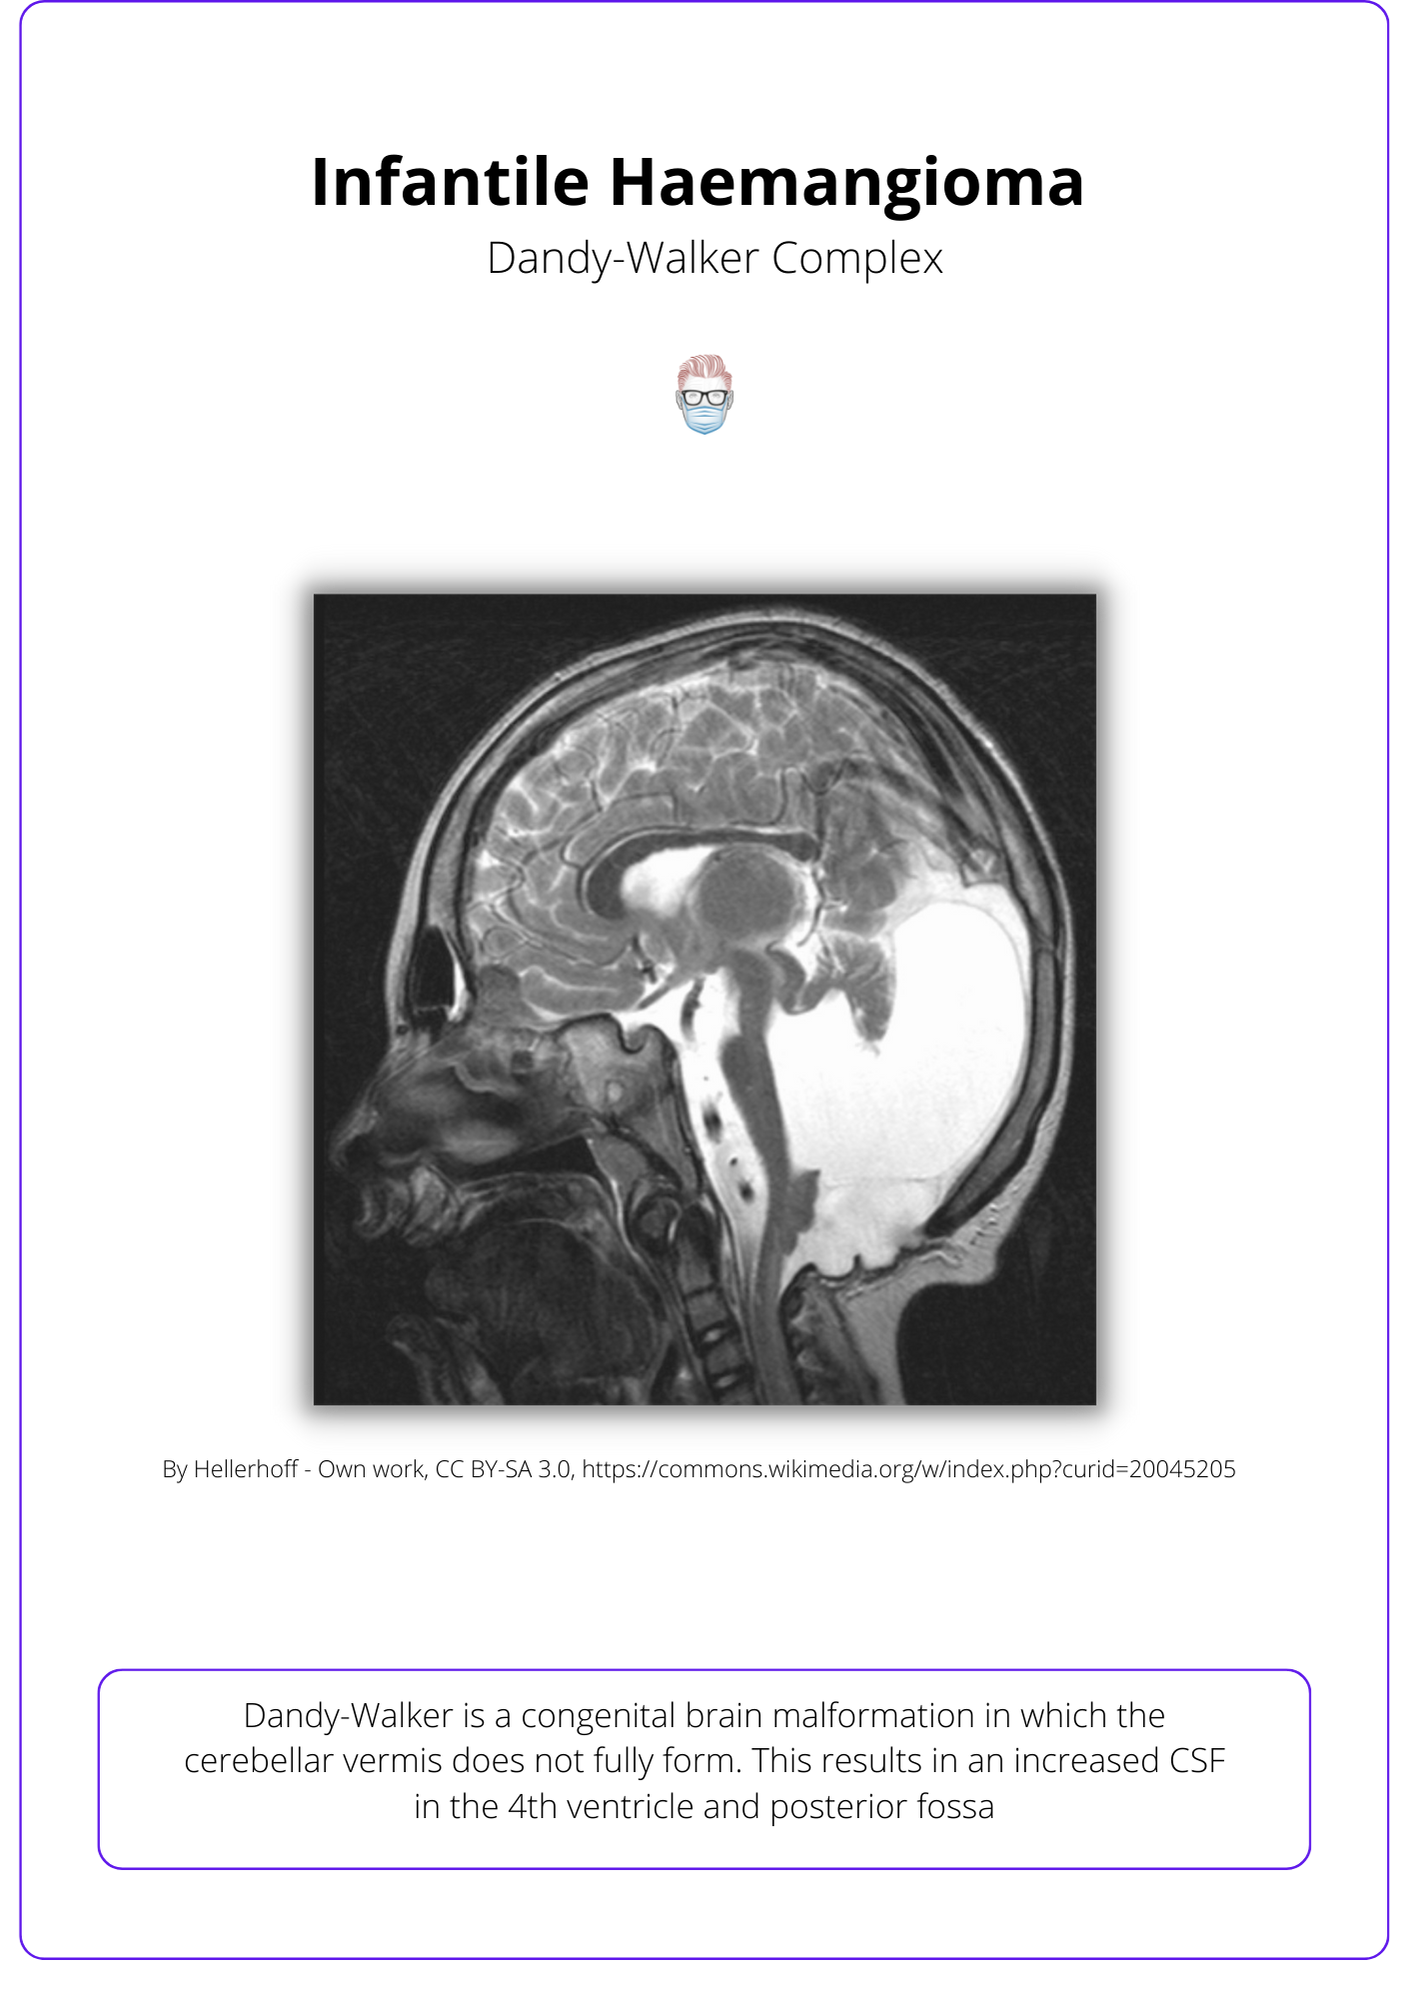

- Posterior Cranial Fossa: Dandy-Walker Complex, hypoplasia, microcephaly

See the below visualization of the Dandy-Walker complex.